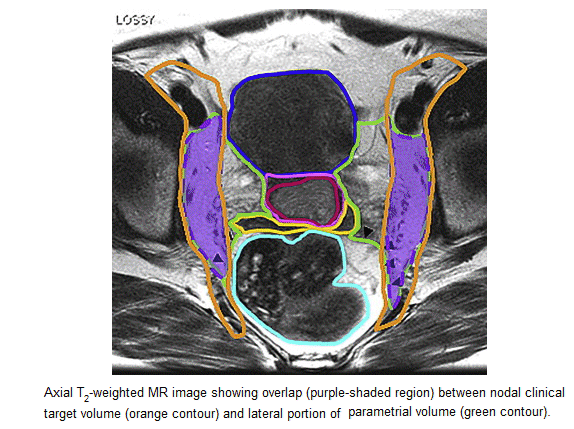

MRI cervix targets

here

and